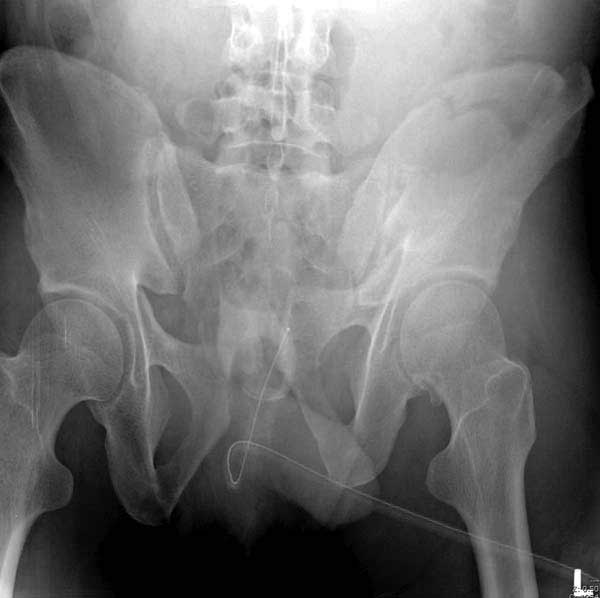

Рецидив смещения - признак несостоятельности фиксации. В первую очередь из-за ранней нагрузки, или когда имеется нестабильность в тазовом кольце. При повреждениях транссакральных структур сзади, фиксация переднего полукольца-симфиза облегчает репозицию, но не гарантирует стабильность. Нестабильное тазовое кольцо ранее или поздно срывает фиксацию симфиза.

Реконструктивные пластины слабые, и для усиления необходимо установить дополнительную верхнюю пластину или оставить передний наружный фиксатор. Предпочтительным для фиксации считаю специальную для симфиза жесткую пластину из набора Joel Matta (Stryker), которая лучше, чем остальные, создает жесткость.

Подробное изучение инлет и оутлет, а также КТ срезов, поможет разобраться в диагностике. Без обследования случай усложнится. Операция непростая, кроме технических навыков, надо иметь стандартные инструменты для операции.